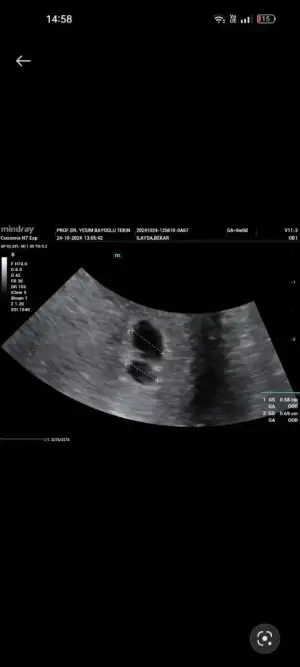

Merhaba bugün ikiz gebeliğe hamile olduğumu öğrendim fakat keselerden büyük olan boş diğerinde bebek gözüktü beta 10447 6 haftalık dedi bilgisi olan varsa yazabilirmj

Eklentiler

• Screenshot_2024-10-24-14-58-07-70_99c04817c0de5652397fc8b56c3b3817.webp

Screenshot_2024-10-24-14-58-07-70_99c04817c0de5652397fc8b56c3b3817.webp

10,7 KB · Görüntüleme: 73